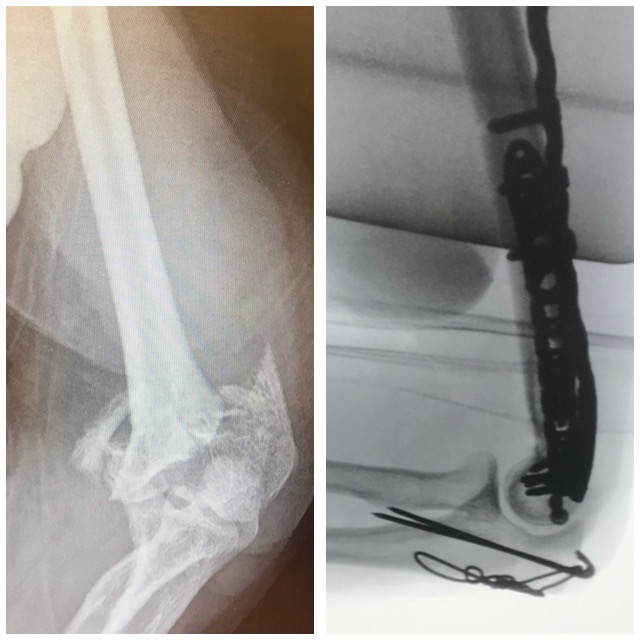

Kyynärpäämurtuma

Ennen – Jälkeen